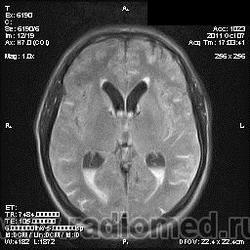

на МРТ - Определяется скопление крови в препонтинной цистерне, в проекции супраселлярной цистерны, в кортикальных бороздах полушарий головного мозга,  в проекции краниоспинального перехода. Выявляется горизонтальный уровень крови в задних рогах боковых желудочков. Боковые, третий желудочки резко расширены. Определяется перивентрикулярное повышение интенсивности сигнала от белого вещества головного мозга. Срединные структуры не смещены. Кортикальные борозды умеренно сглажены. Сильвиев водопровод прослеживается на всем протяжении. Отмечается смещение дна третьего желудочка каудально, с резким уменьшением размеров супраселлярной цистерны; базальные цистерны уменьшены в размере.

В проекции базальной артерии определяется аневризма размером до 4х6 мм.